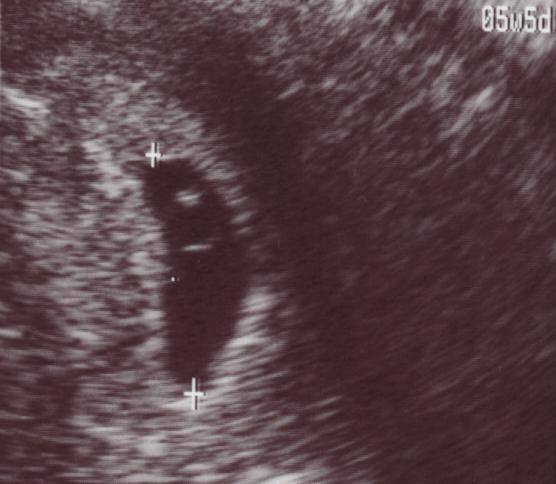

ダンナと二人で産婦人科へ。

先生に診てもらったところ、やっぱり妊娠していた。